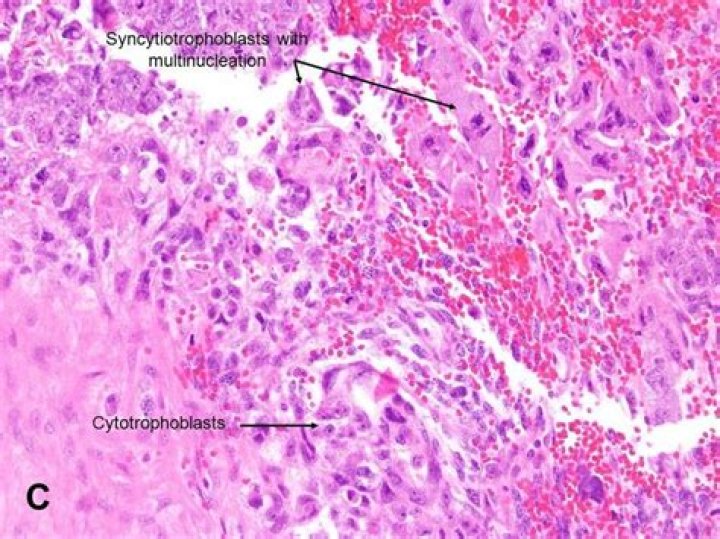

Are chorionic villi seen in choriocarcinoma?

By definition, chorionic villi should not be present in choriocarcinoma (with the exception of intraplacental choriocarcinoma, discussed later). The trophoblast of choriocarcinoma shows marked cytologic atypia (syncytiotrophoblast—somewhat less than other types of trophoblast) (see Fig.